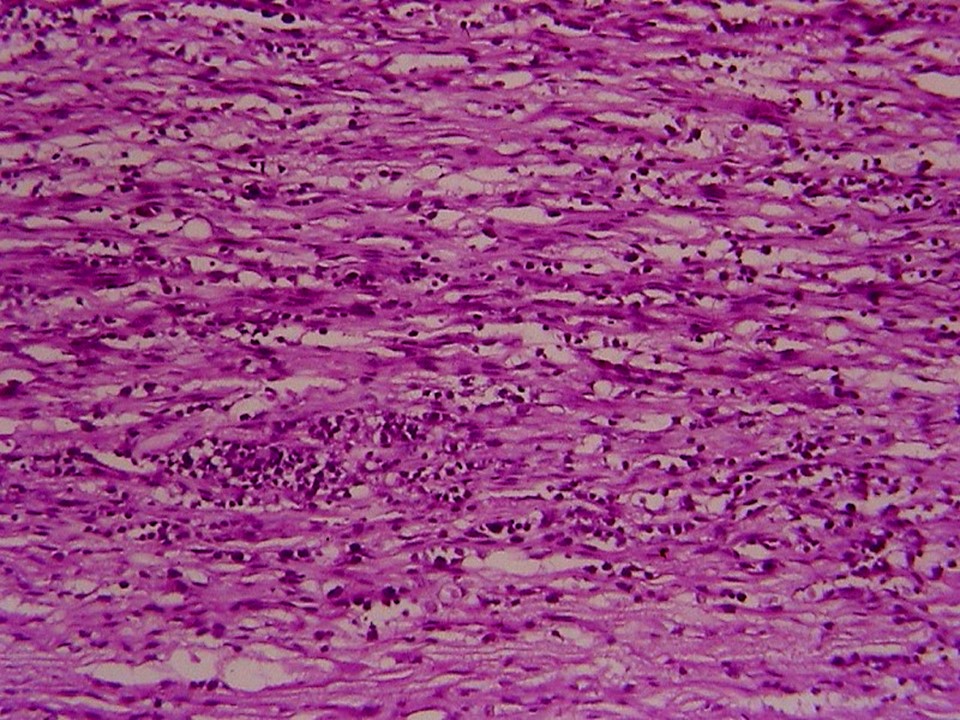

疾病中文名稱:馬立克病

疾病英文名稱:Marek's disease

影像說明:翼神經受侵犯而翅膀下垂,坐骨神經受侵犯呈劈腿狀